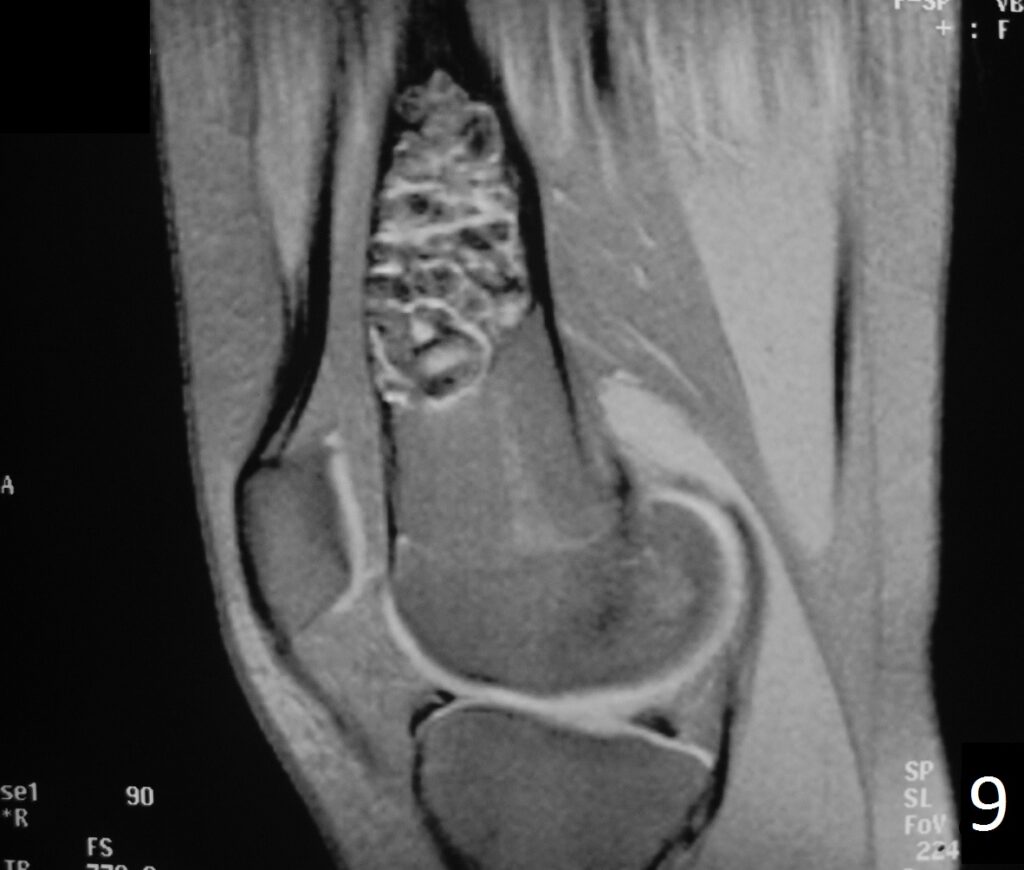

MRI

• Low- signal on T1 (Fig. 8)

• Variable heterogeneneous signal on T2 (Fig. 9).

• Possible extensive hypercellular fibrous tissue and hemosiderin seen on T2

• Can be useful for demonstrating an aneurysmal bone cyst component

Fig. 9

Fig. 6-9: Sagittal T1 (Fig. 6) and T2 (Fig. 7) MRI of the knee demonstrates a fibrous cortical defect. Axial T1W (Fig. 8) and T2W (Fig. 9) show a heterogeneous lesion on distal femur, compatible with nonossifying fibroma.